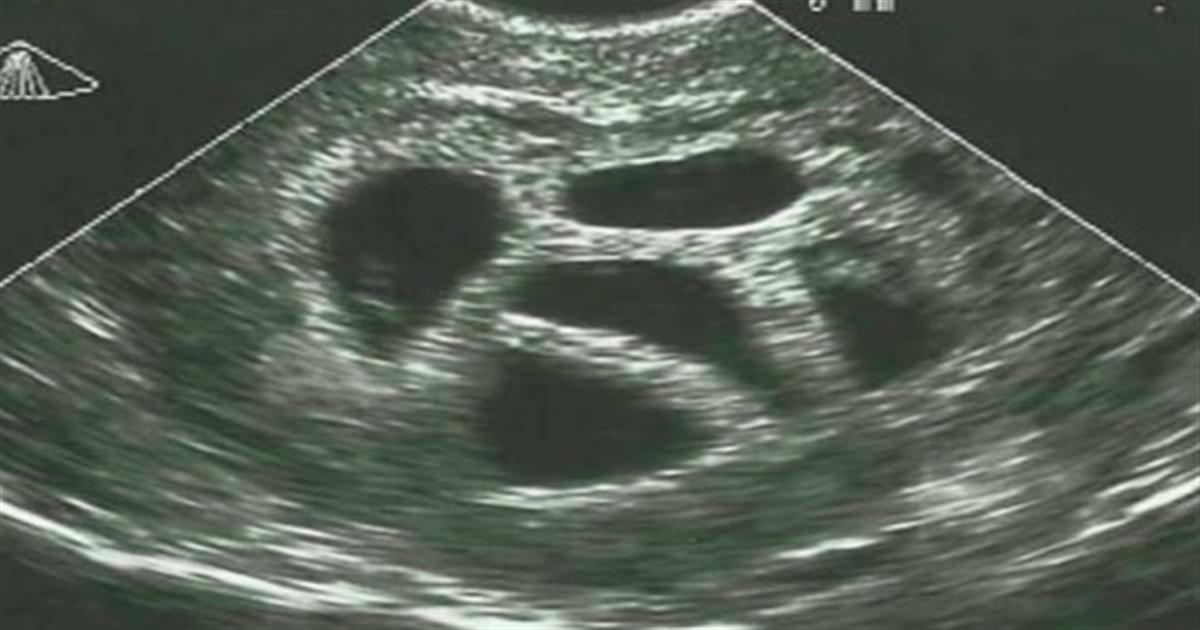

Δεν ήταν έγκυος ούτε σε ένα, ούτε σε δύο αλλά σε πέντε μωρά! Είναι κάτι σπάνιο να συμβεί, αλλά για την Σούζαν έγινε πραγματικότητα. Η 28χρονη τότε μητέρα, συμβουλεύτηκε από τον γιατρό της να ματαιώσει την εγκυμοσύνη, και να κάνει επιλεκτική έκτρωση, αλλά εκείνη αρνήθηκε. Δείτε την φωτογραφία 20 χρόνια μετά!

Αλλά τι είναι μια επιλεκτική έκτρωση; Είναι μια μορφή θεραπευτικής έκτρωσης. Ένα ή περισσότερα έμβρυα αφαιρούνται για να αυξήσουν την πιθανότητα επιβίωσης για τα υπόλοιπα. Η επιλεκτική άμβλωση χωρίς ιατρικούς λόγους που βασίζονται μόνο στο φύλο είναι παράνομη.

Η Σούζαν αρνήθηκε να το κάνει χωρίς δισταγμό και οδηγήθηκε σε ειδικό. Ωστόσο, πήρε την ίδια συμβουλή: να συνεχίσει την εγκυμοσύνη με μερικά από τα έμβρυα. Η Σούζαν και ο σύζυγός της επέμειναν στην επιλογή τους και δεν θα το μετάνιωναν αργότερα.